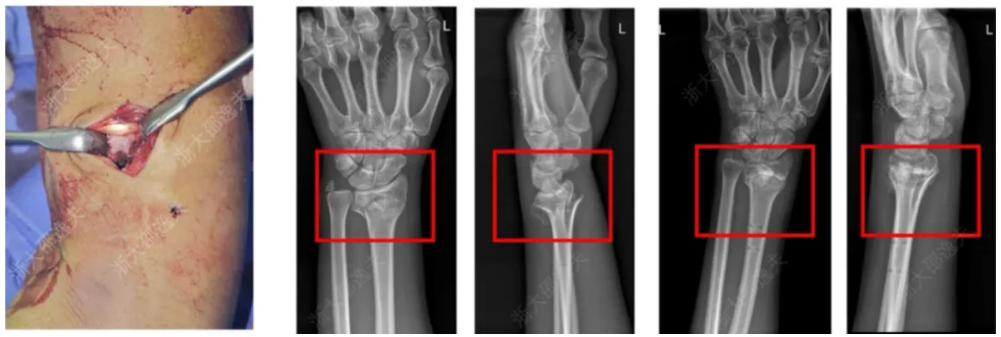

它在多家医院150余例受试病例中展现出了良好的安全性和有效性,各项指标达到预设标准。其中一位年轻工人因外伤致腕部粉碎性骨折,为避免传统的钢板内固定手术方案,医生通过一个2-3厘米的微创切口注入了“骨02”,便黏合了碎骨。术后复查显示,患者骨折愈合良好,手腕功能得以恢复。

来源:见水印